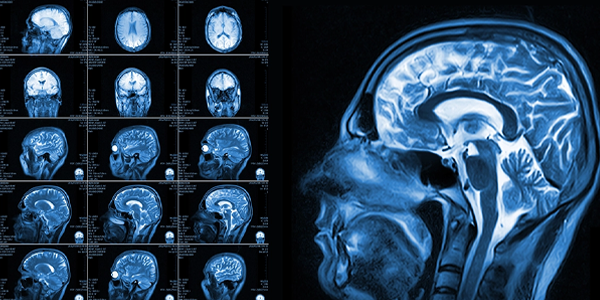

Chiari Malformasyonu Nasıl Teşhis Edilir?

Chiari malformasyonu teşhisi için aşağıdaki yöntemler kullanılabilir:

• Manyetik Rezonans Görüntüleme (MR): MR, Chiari malformasyonunu teşhis etmek için kullanılan en önemli görüntüleme yöntemidir. MR, beyin ve omuriliğin detaylı görüntülerini elde ederek beyinciğin yer değiştirme miktarını ve BOS akışını değerlendirmeye olanak tanır.

• Bilgisayarlı Tomografi (BT): BT, kemik yapıları görüntülemek için kullanılan bir görüntüleme yöntemidir. Chiari malformasyonunda kafatasının ve omurganın kemik yapılarını değerlendirmek için kullanılabilir.

• Diğer Testler: Nörolojik muayene, denge testleri ve görme testleri gibi diğer testler de teşhisi desteklemek için yapılabilir.